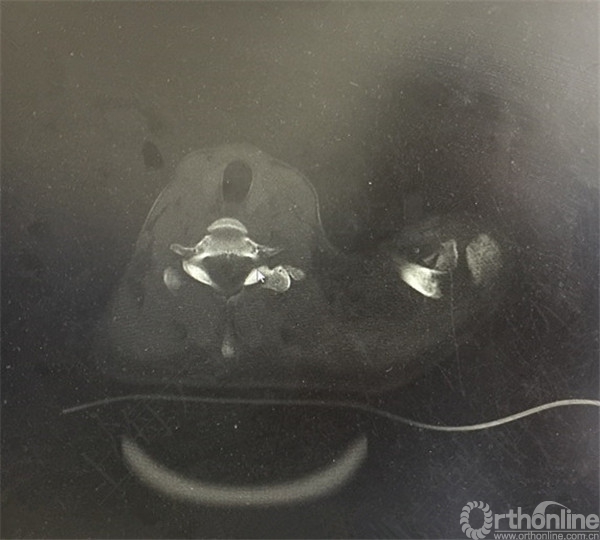

CT示:左锁骨远端骨折,远端骨块向前下方移位。